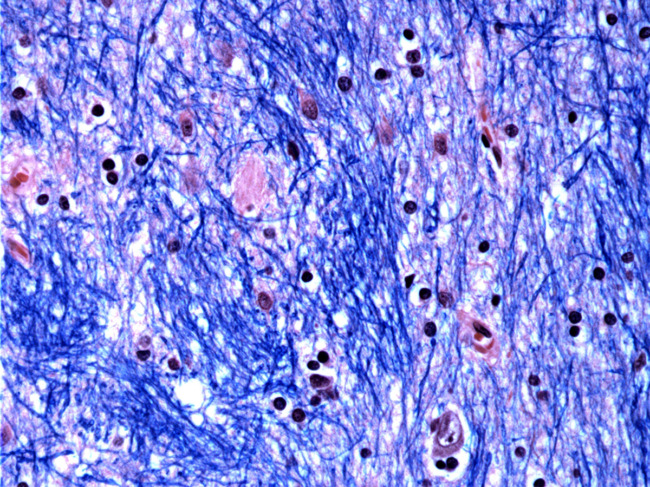

Histological staining of the caudate nucleus from a person with Huntington’s disease.

Huntington’s neurodegeneration starts at 150 repeat expansions

Having 35 copies of the CAG triplet in the gene that causes Huntington’s disease is not a problem. Inheriting 40 could be a sign that goes unnoticed for decades, until reaching 80. From there, the process accelerates and neural death occurs when reaching 150 repeats. Huntington’s disease neurodegeneration is not determined by what, but by how much, according to a study conducted at the Broad Institute. Read More